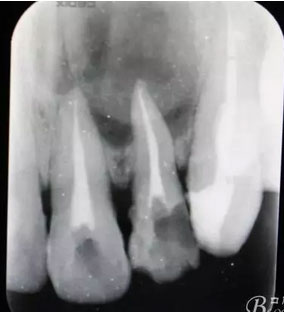

圖3.根管治療完成后的影像檢查: